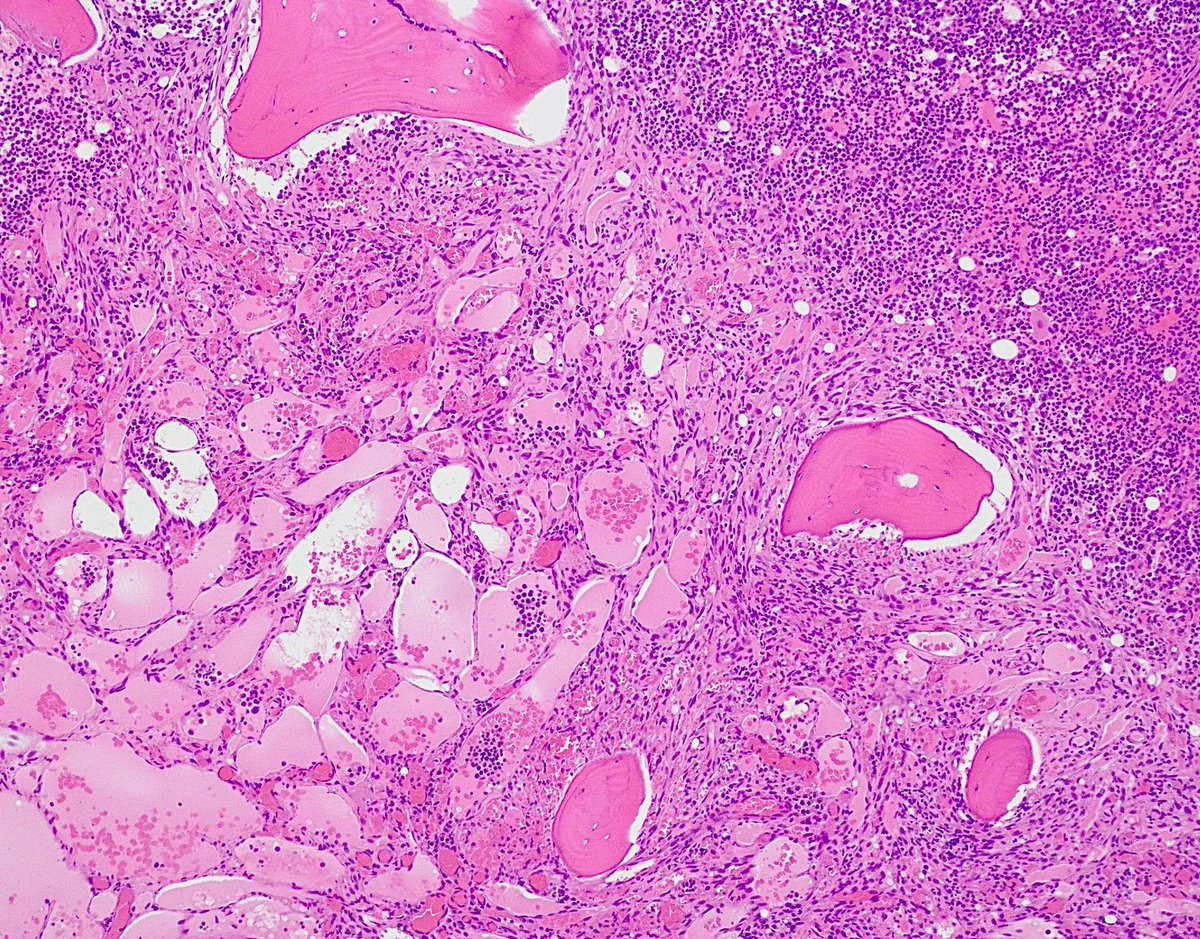

Extensive Kaposi infiltration in bone marrow in a patient with HIV Kaposi Sarcoma Bone Marrow In all forms and cases, the etiologic agent is human. Kaposi’s sarcoma (ks) is a rare, malignant, multilocular vascular disease originating from lymphatic endothelial cells that can primarily affect the skin and. Kaposi sarcoma is a disease in which cancer cells are found in the skin or mucous membranes that line the gastrointestinal (gi) tract, from mouth to anus, including. Kaposi Sarcoma Bone Marrow.

Jerad Gardner, MD on Twitter "RT Gloria_SuraMD Bone marrow biopsy Kaposi Sarcoma Bone Marrow Malignant vascular neoplasm of intermediate behavior. Kaposi’s sarcoma (ks) is a rare, malignant, multilocular vascular disease originating from lymphatic endothelial cells that can primarily affect the skin and. Kaposi sarcoma is a disease in which cancer cells are found in the skin or mucous membranes that line the gastrointestinal (gi) tract, from mouth to anus, including the stomach and. In. Kaposi Sarcoma Bone Marrow.